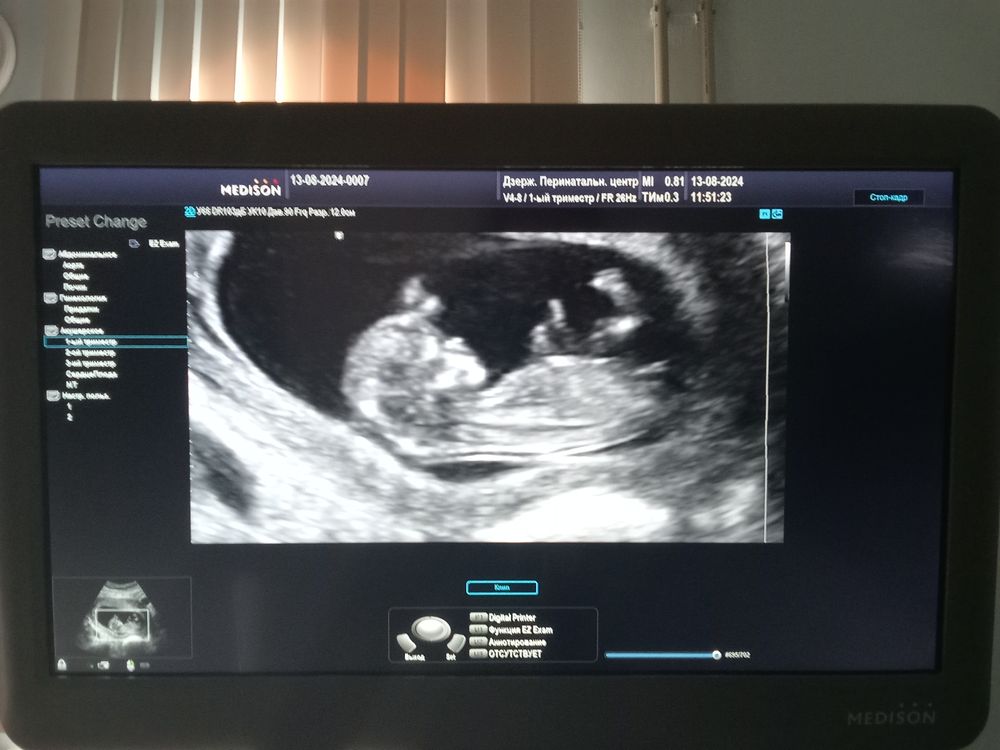

1 скрининг

на девочку похож)

12 акушерских недель Правильно ли считаю